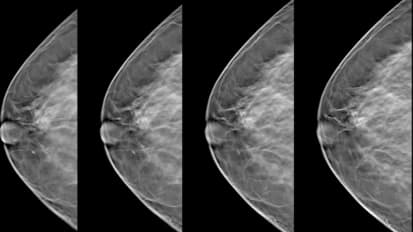

Clinical Minutes: 3D Tomosynthesis Mammography

Linda Womack, John Muir Health Imaging Service Line Director, explains 3D Tomosynthesis Mammography and outlines the patient benefit.

Breast Imaging: 3D Mammography Arrives at John Muir Health

Digital Breast Tomosynthesis (DBT), also known as 3-D mammography, is a breakthrough in imaging that provides a clearer, more accurate view compared to digital mammography alone.